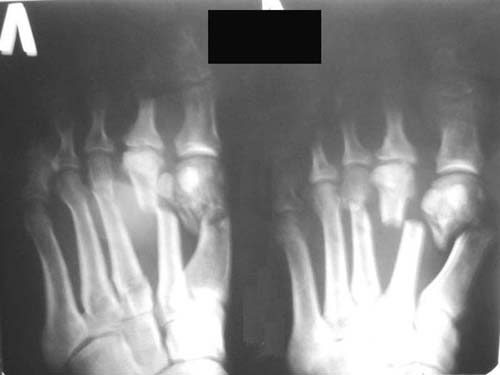

Man, 57 y.o., got a trauma in the coal mine.

Diagnosis: smash of the front parts of both feet, multiple open fractures of metatarsus bones and phalanxes of toes, contused-scalped wounds.

Right: scalped wound on the sole (10*8cm), partial injury of toes flexion tendons, incomplete tearing off of I-III toes (on the back piece);

Left: lacerated-contused wound on the back surface (4*7cm) with smashed edges, wound on the heads of metatarsus II-III bones (4*2cm), contused wound on the sole (2*1cm).

Left foot

Right foot